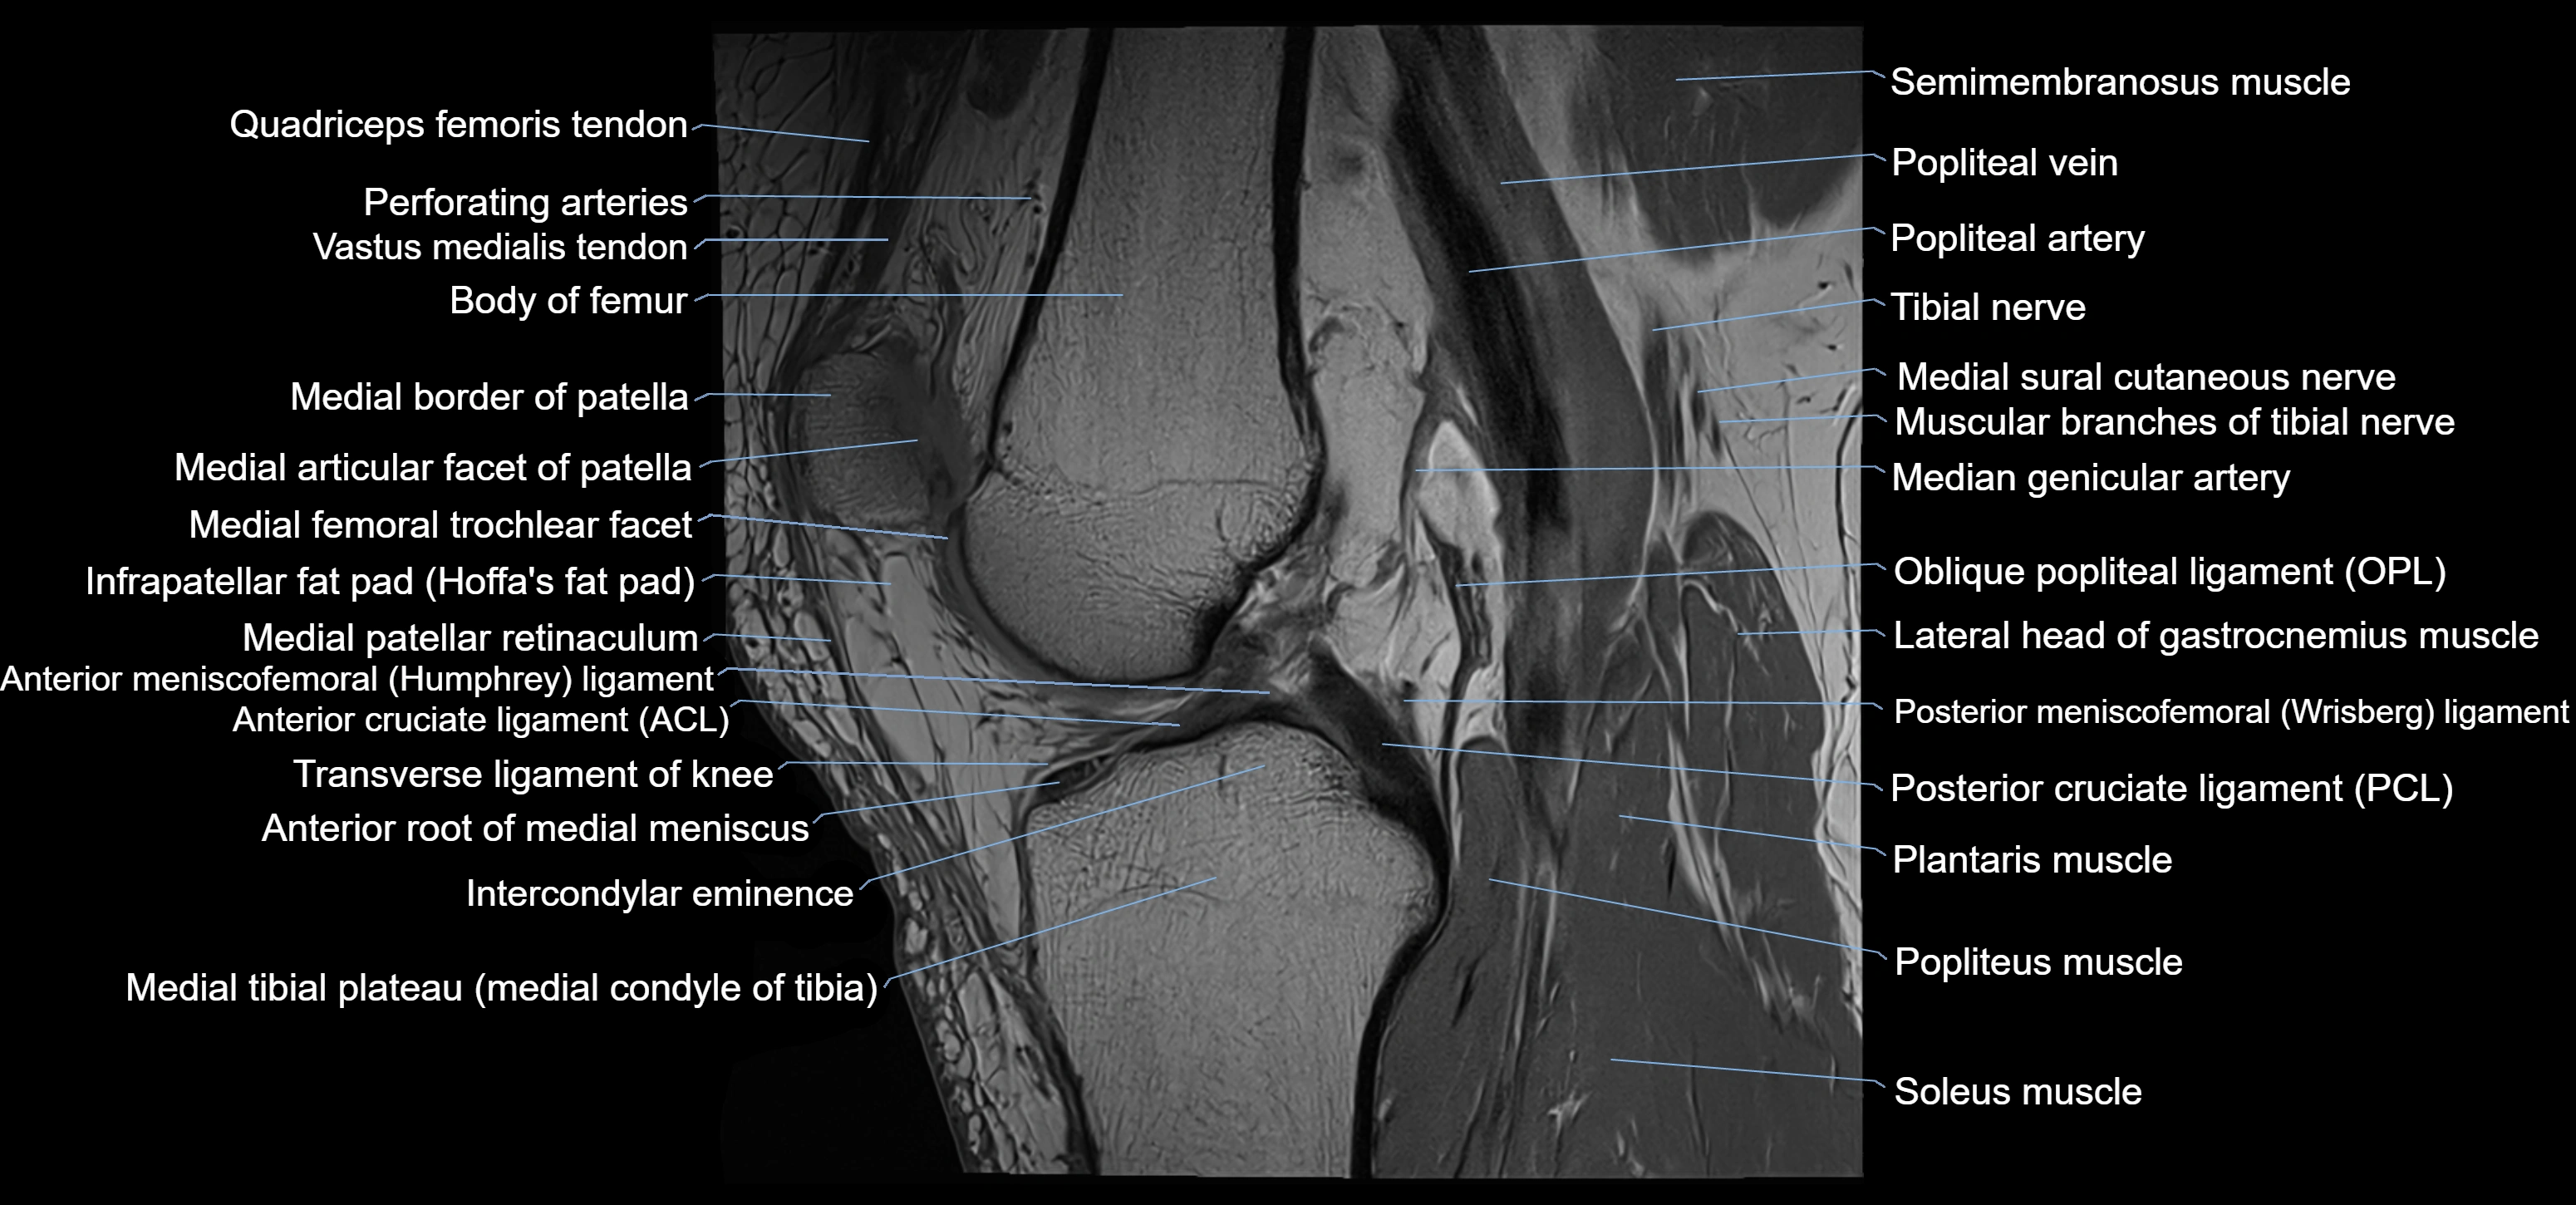

- Anterior cruciate ligament

- Anterior meniscofemoral ligament

- Anterior root of medial meniscus

- Body of medial meniscus

- Knee Joint

- Oblique popliteal ligament

- Patellar tendon (patellar ligament)

- Popliteal artery

- Popliteal vein

- Popliteus muscle

- Posterior cruciate ligament

- Posterior meniscofemoral ligament

- Soleus muscle

- Transverse ligament of knee